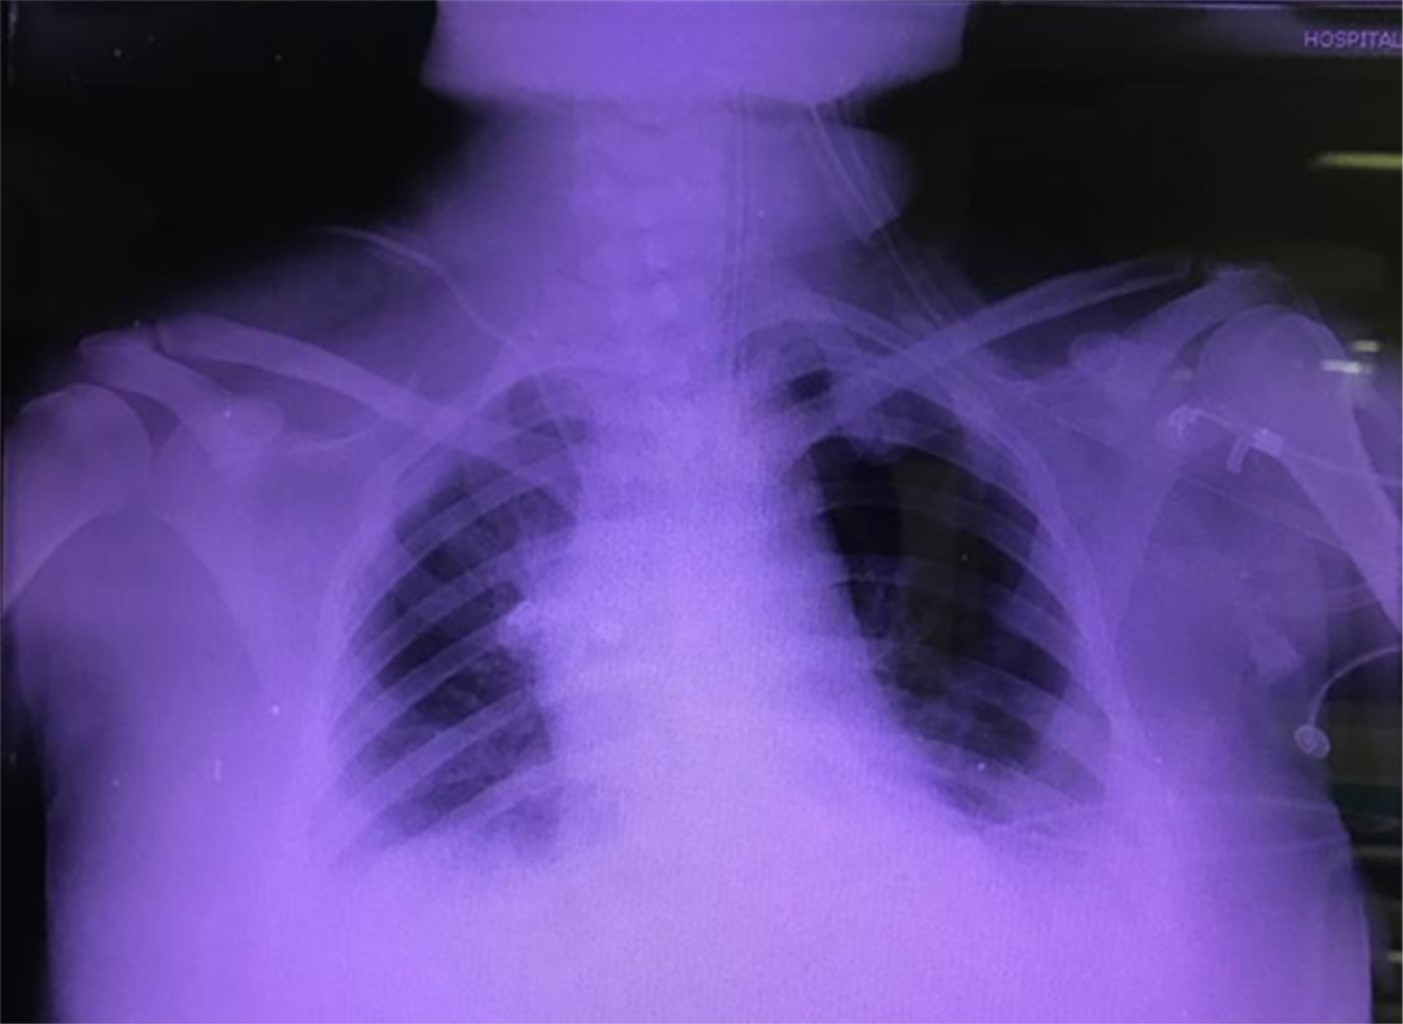

Acquired hemophilia A in pregnancy. Clinical case of critical medicine in obstetrics due to extreme morbidity and its perioperative transdisciplinary approach

Reyes-Mendoza LE, Castorena-de AR, Enríquez-López R, Ángeles-Vázquez MJ, Anaya-Herrera J, Flores-Cánovas Y, Sevilla-Cano A, Malagón-Reyes R, Rodríguez-Roldán M, Mendieta-Zerón H, Díaz LM, Carrillo-Esper R, Briones-Garduño JC

The identification of multiple risk factors that predispose to bleeding during the obstetric event, such as acquired hemophilia, which is a disorder that develops due to the generation of autoantibodies that inhibit coagulation factors, the objective interpretation of routine laboratory tests , the development of systematized thinking in diagnostic-therapeutic integration by health personnel, and the provision of hospital pharmacological resources, is what frequently determines the prognosis in obstetric patients with extreme morbidity who require multidisciplinary care in the different hospital units of the health sector of our country. The objective is to present a clinical case of extreme morbidity due to acquired hemophilia, its clinical presentation, evolution and fatal outcome. A case referred from another unit of the ISEM (Instituto de Salud del Estado de México) Health Sector, treated at the Obstetric Intensive Care Unit of the "Mónica Pretelini Sáenz" Hospital, is presented, highlighting the importance of diagnostic-therapeutic integration, and the multifactorial interaction of variables related to its fatal outcome. Conclusions: Ignorance of the pathology, delay in diagnosis, multiple conditioning procedures of iatrogenic hemorrhage and the limitation in therapeutic resources are factors that contribute to a fatal outcome.

Figure 1